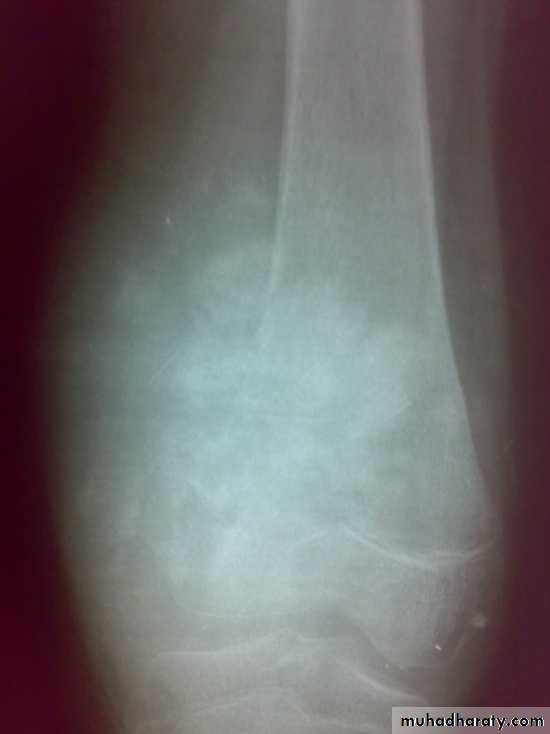

X-ray show eccentric osteolytic lesion in the end of long bone ,subchondral, trabeculated (soap bubble appearance). The cortex is thin, expanded or even perforated.